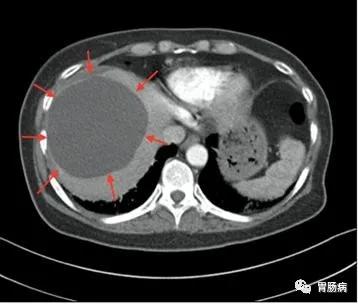

超声是最有效的初检手段,如果需要进一步鉴别,可以再做CT或者核磁共振,甚至穿刺针吸活检等检查。CT如下图所示

大多数肝囊肿无明显症状,仅在B超或CT检查时偶然发现,少数可表现为餐后饱腹感、食欲减退、腹痛腹胀等,尤其是体积较大的肝囊肿。

最常见的单纯性肝囊肿,在超声检查中表现为肝脏内部出现的澄清液体的囊性结构,偶然体检发现的无症状患者不需要对肝囊肿进行治疗,单纯性肝囊肿也不需要反复做检查。